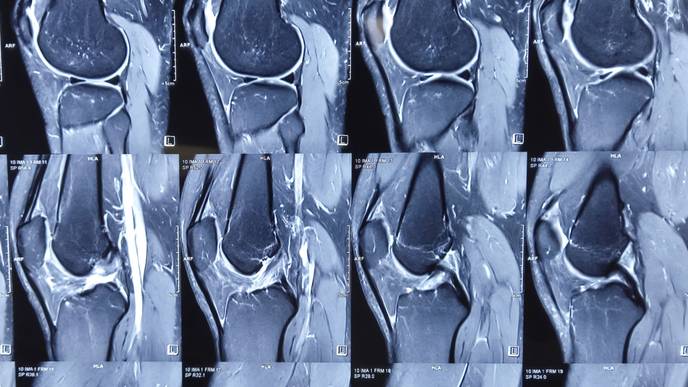

In this case report, researchers Mohamed A. Gouda, Maria A. Zarzour, Ara A. Vaporciyan, Kalevi Kairemo, Hubert H. Chuang, and Vivek Subbiah from The University of Texas MD Anderson Cancer Center and Sarah Cannon Research Institute discuss the case of a patient with a EWSR1-NFATC2 fusion positive bone sarcoma who had exceptional tumor control through using pazopanib and surgery for an overall duration exceeding 5 years. The report also reviews the literature on EWSR1-NFATC2 translocation-associated sarcomas and use of pazopanib in bone sarcomas.